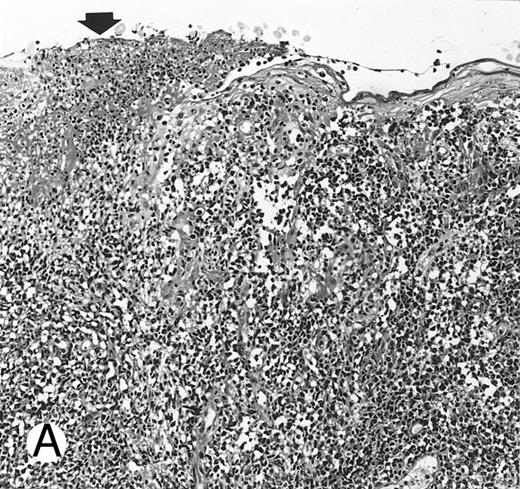

Nasal-type NK/T-cell lymphoma presenting as nodular skin lesion (case no. 28). (A) The skin shows focal necrosis of the epidermis and ulceration (arrow). (B) The lymphoid infiltrate in the dermis shows angiocentricity, as evidenced of the higher density of cells in the expanded walls of the blood vessels (arrows).

Histologically, the lymphomatous infiltrate was diffuse or patchy, with angiocentric and angiodestructive growth being observed in 30 cases (88.2%) (Figs 1 and 2). The cytologic composition was variable from case to case, including predominance of small cells, medium-sized cells, or large cells, or a mixture of these cell types (Fig 2 and 3). The tumor cell nuclei frequently showed irregular foldings and granular chromatin (Fig 2B). The larger cells possessed distinct nucleoli. The cytoplasm was moderate in amount and often pale. Karyorrhexis was usually prominent. Zonal tumor cell death, focal or confluent, was evident in 27 cases. In the 14 cases for which Giemsa-stained touch preparations were available, azurophilic granules could be identified in at least some of the neoplastic cells.